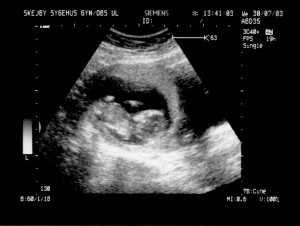

Ultralydsskanning den 30. juli 2003

Vi har i dag været på Skejby Sygehus og få foretaget en ultralydsskanning af baby. Der var kun én (pyh)! Baby blev målt og gennemset for eventuelle misdannelser. Der blev set efter at kraniet var begyndt at blive dannet og at der var to hjernehalvdele. Vi så to arme og to ben og der var fem fingre på den hånd vi så. Vi så også hjertet slå. Til sidst blev der blev målt bredden på nakkenfolden for at vurdere risikoen for mongolisme. Man kan læse mere om ultralydsskanningen her.

Konklussionen var, at alt var som det skulle være, men baby selv var ikke tilfreds. Den lå og sparkede og slog omkring sig og tog sig til hovedet.

Du kan se de billeder vi fik fra skanningen herunder.